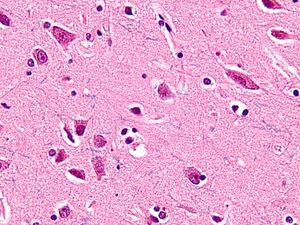

العصبونات المغزلية Spindle neurons، تسمى أيضاً عصبونات ڤون إكونومو von Economo neurons (VENs)، هم رتبة معينة من العصبونات التي تشارك في نقل الإشارات في الجهاز العصبي، وتتميز بجسم على شكل مغزل كبير، ينحف تدريجياً حتى يصبح محور عصبي وحيد القمة في اتجاه، ويصبح زائدة مشجرة dendrite واحدة في الاتجاه المقابل. وبينما الأنواع الأخرى من العصبونات تنحى لأن يكون لها العديد من الزوائد المشجرة، فإن الشكل القطبي للعصبونات المغزلية يـُعد فريداً، وقد تم العثور عليه فقط في منطقتين محدودتين في مخ hominids - الفصيلة التي تضم البشر والقردة العليا. وتوجد الخلايا المغزلية أيضاً في أمخاخ الحوت الأحدب، الحوت الزعنفي، الحوت القاتل والحوت المنوي[1][2], وفي أمخاخ الفيل الافريقي و الأسيوي.[3] الاسم عصبون ڤون إكونومو يحمل اسم مكتشفه، كونستانتين ڤون إكونومو Constantin von Economo (1876-1931).